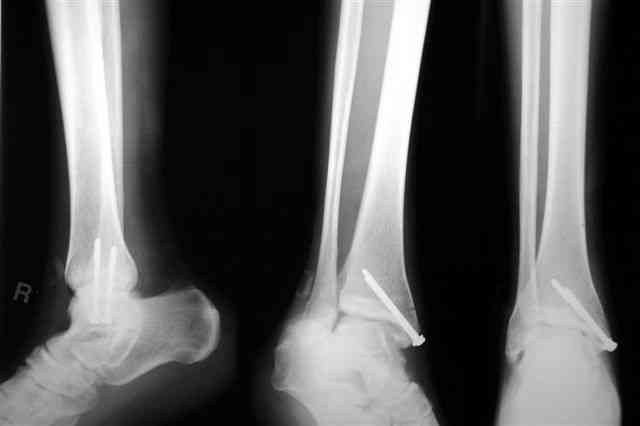

В приложении отправляю послеопер. снимки бедра и лодыжки обсуждаемого вчера больного.